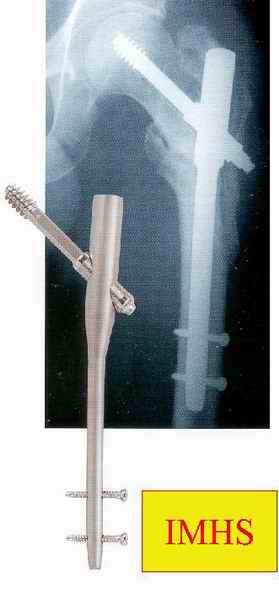

Большие преимущества у интрамедуллярных штифтов, метод хорош и можно произвести из минимального доступа, но во время операции необходимо контролирование варуса, затем приступить к блокированию.

слайды:

Long TFN

Short TFN

IMHS

DePuy Trochanteric Nail

Контролировать варус

Ap pelvis Rt sub-intra trochanteric Fracture, AP Rt hip, Postop Blade Fixation